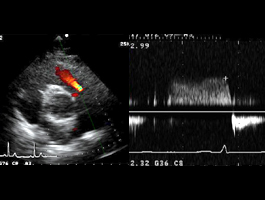

左室流入血流波形

左室流入血流波形パターン。

E/A:2.1、DcT:138msecと短縮しており拘束型を示している。

偽正常化の場合、左室流入血流波形のみでは正常との鑑別は不可能である。